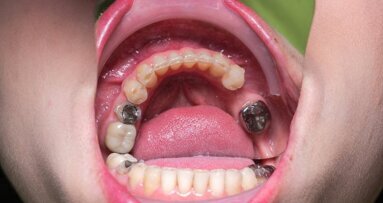

Conforme relatado pelo Dental Tribune International em janeiro, a proibição da UE sobre a amálgama levou a preocupações sobre problemas na cadeia de suprimentos no Reino Unido. O amálgama é o material mais comumente usado para obturações permanentes pelo National Health Service (NHS), de acordo com a British Dental Association (BDA). Como a Irlanda do Norte tem o maior número de dentes obturados proporcionalmente, o país teria sido a nação mais afetada do Reino Unido. Embora a BDA geralmente apoie a redução do amálgama, ela chamou a rápida eliminação do amálgama em práticas odontológicas de inviável e injustificável.

Uma pesquisa feita pela filial da Irlanda do Norte da BDA em março revelou que uma proibição de amálgama a partir de 2025 teria um impacto significativo nas práticas odontológicas. De acordo com a pesquisa, 88% dos dentistas relataram que tal proibição os levaria a reduzir ou encerrar completamente seu compromisso com o NHS, 92% esperavam aumento nos custos dos serviços do NHS e 91% dos entrevistados indicaram que pacientes com maiores necessidades seriam afetados.